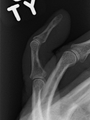

- A mallet finger without an associated fracture